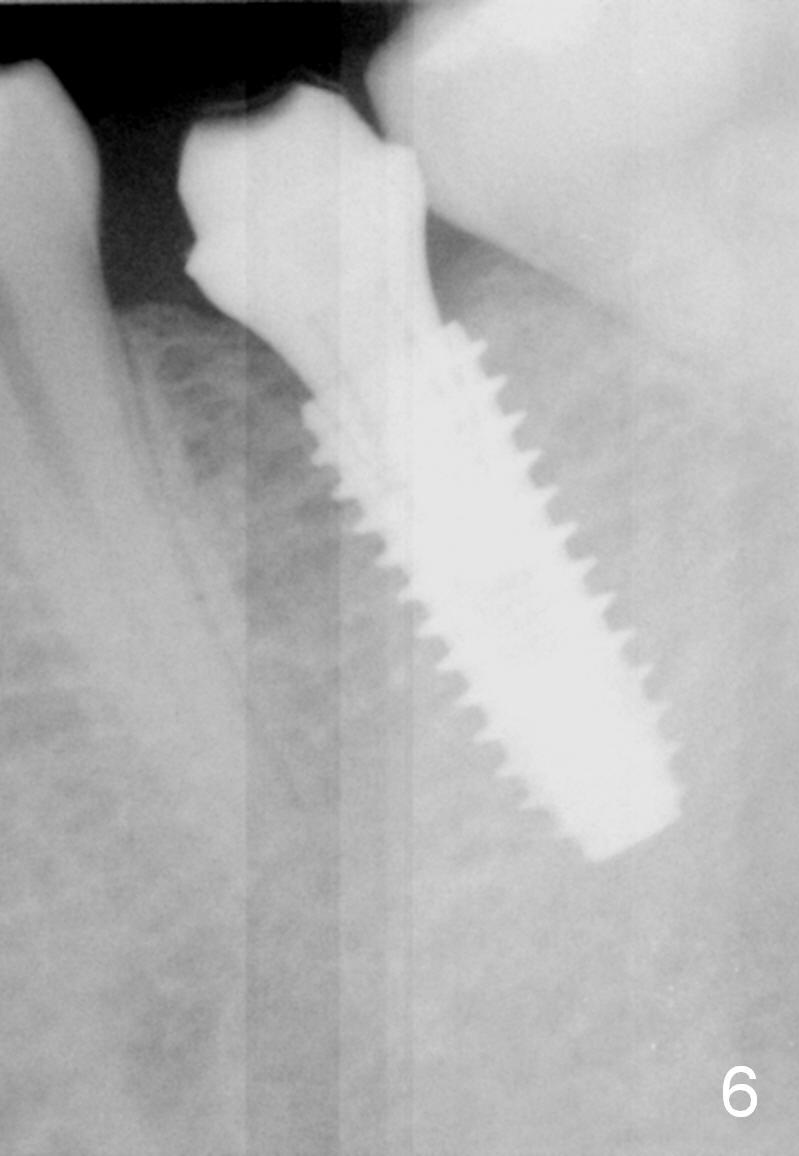

A 31-year-old woman agrees to have implant at #19 (Fig.1) after redoing MOL composite at #20 (Fig.2 *). The edentulous mesiodistal space is narrow (~ 6 mm in Fig.3). If the buccolingual bone width is found to be good after incision, a large implant is preferred. To gain space mesiodistally, the proximal surfaces of the neighboring teeth will be reduced (Fig.2 blue curved lines).

In fact, the buccolingual width of the ridge is sufficient to have a 4.5x11.5 mm implant placed (Fig.4,5, D3 bone, <35 Ncm). Proximal reduction is done before and after placement of a 5.5x4(3) mm abutment. Heavy abutment height adjustment is provided as well as the opposing prior to immediate provisional.